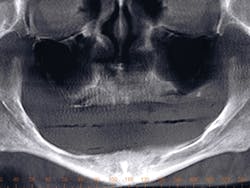

5. Observe the detail of the final impression.

6. Note the impression with the impression coping-analog complex. The stability of making the cast without movement of the coping-analog complex is minimized.